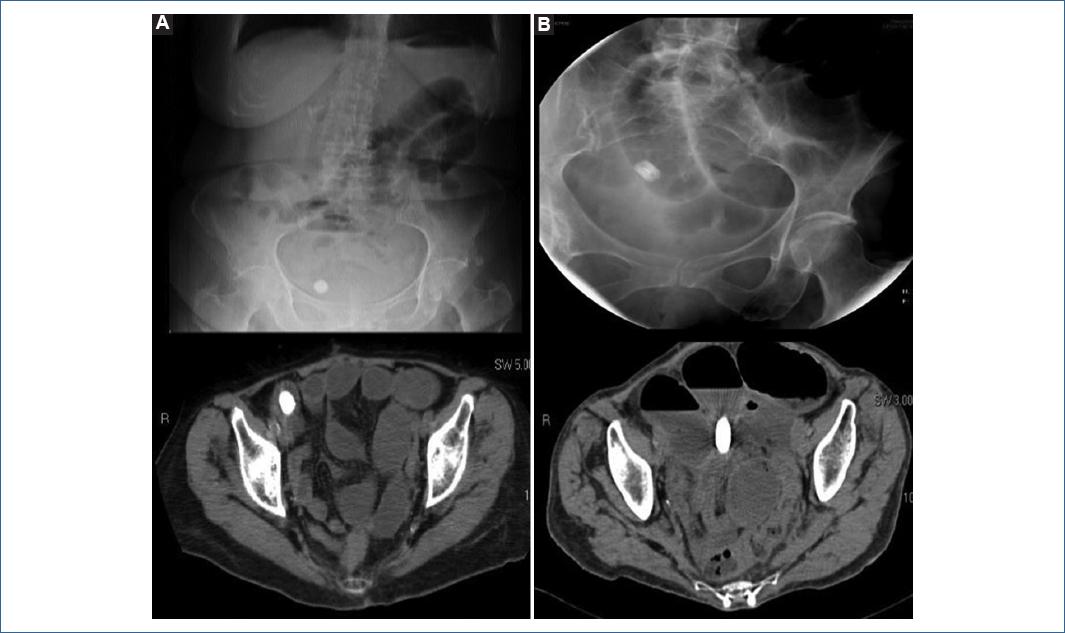

Cuatro pacientes expulsaron la cápsula de manera natural, mientras que dos presentaron retención de la misma. En los pacientes que presentaron excreción natural, solo uno la expulsó en las primeras 30 horas, por lo cual no requirió estudio de imagen. Tres pacientes la expulsaron después de 30 horas, por lo que en dos se realizó radiografía de abdomen y se complementó con tomografía de abdomen observando cápsula en recto y ciego respectivamente, mientras que en otro paciente se documentó la cápsula en recto por radiografía de abdomen (Imagen 1A, 1B y 1C respectivamente). De éstos, uno expulsó la cápsula después de 72 horas, la cual se encontró íntegra. Dos pacientes presentaron retención de la cápsula en íleon, en un pacientes fue retención asintomática documentada por tomografía y otro paciente desarrollo oclusión intestinal que resolvió espontáneamente (Imagen 2A y 2B, respectivamente).

Imagen 2 Estudios de imagen que demuestran la localización de la cápsula de patencia. A: Radiografía y tomografía computarizada de abdomen con presencia de cápsula retenida en íleon, sin datos de oclusión. B: Radiografía y tomografía.

En los dos pacientes que presentaron retención de la CP se documentó enteropatía por radiación mediante enteroscopia, esto de acuerdo a las recomendaciones de evitar el uso de VCE posterior a un estudio de patencia negativo.

Caso 4. Paciente femenino de 70 años, con antecedentes de cáncer cervicouterino, tratada con histerectomía radical con salpingooforectomía y radioterapia. Enviada a evaluación por anemia por deficiencia de hierro, como síntomas agregados diarrea crónica y pérdida de peso. Se realizó tomografía de abdomen sin observar zonas de estenosis o transición, o áreas de inflamación activa. Endoscopia superior y colonoscopia sin alteraciones relevantes. Por antecedente quirúrgico y tratamiento con radioterapia se administró cápsula de patencia, la cual presentó alto riesgo de retención de cápsula endoscópica (enteropatía por radiación) se decidió dar cápsula de patencia tras lo cual se observó retención de la cápsula en íleon. Por los hallazgos, se realizó estudio de enteroscopia retrográda diagnosticando enteropatía por radiación y zona de subestenosis en íleon distal con diagnóstico histopatológico de ileítis aguda inespecífica.

Caso 5. Paciente femenino de 72 años, con antecedente de cáncer cérvico uterino, tratada con histerectomía radical con salpingooforectomía y radioterapia. Fue enviada a evaluación por hemorragia de tubo digestivo caracterizada por melena. Se realizaron endoscopia superior y colonoscopia sin evidencia de alteraciones. Por el antecedente de radioterapia se realizó cápsula de patencia. Aproximadamente 18 horas después de la ingestión, la paciente presentó suboclusión intestinal. A las 30 horas se realizó estudios de imagen observando retención de la cápsula en íleon distal. Finalmente se realizó estudio de enteroscopia retrógrada diagnosticando enteropatía por radiación y subestenosis en íleon distal, con diagnóstico histopatológico de íleitis aguda y crónica inespecífica.